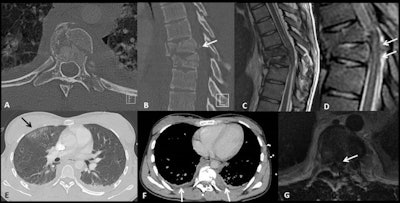

"Patients with high-energy trauma and a high risk of multisystemic involvement should generally be managed as polytrauma patients, and multidetector CT is currently the imaging technique of choice," they wrote. "MRI has a fundamental role in the evaluation of severe spine injuries before neurosurgical intervention and is the modality of choice for assessing the real extent of brain damage after severe head trauma."

Angiography with embolization has a pivotal role in the treatment of vascular and parenchymal injuries, they pointed out. "Radiography is the first-line tool in the evaluation of a bony injury of the upper and lower extremities. Ultrasound still has an important role in minor blunt abdominal trauma, particularly in the pediatric population due to the absence of ionizing radiation."